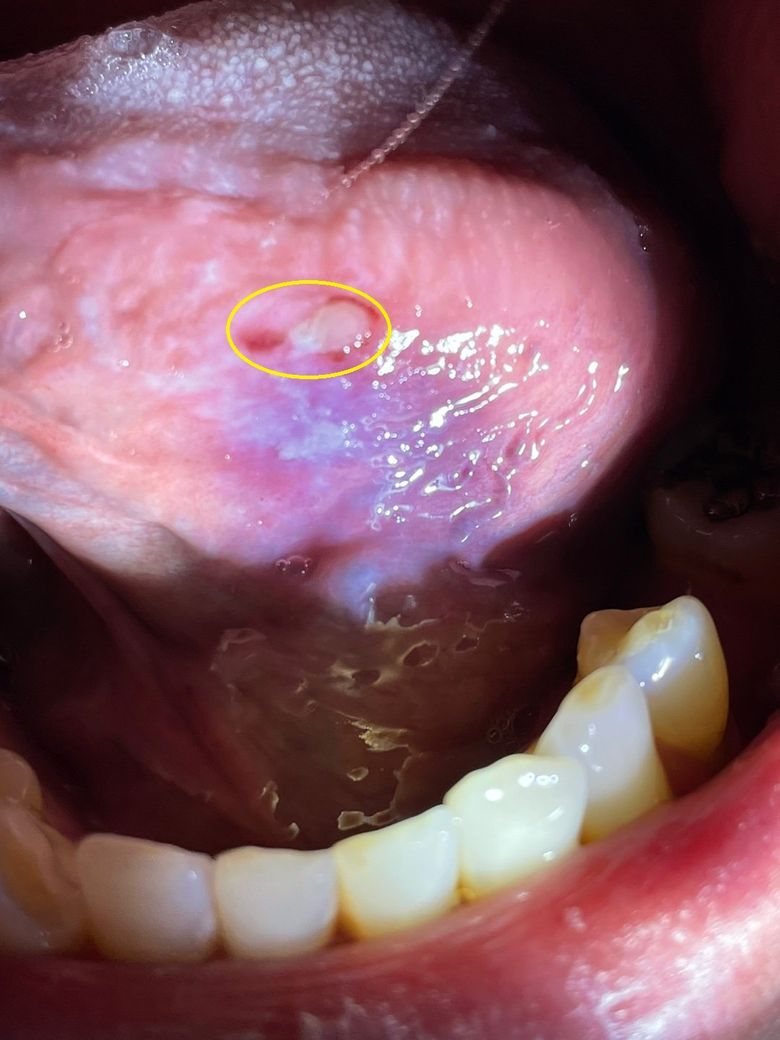

사진으로 보아 혀밑에 생긴 구내염으로 보입니다. 보통 구내염은 작은 원형으로 약간 노란색을 띄게 됩니다.

구내염은 1주일 정도 지나야 아물게 됩니다. 혀를 깨물어 생긴 상처는 2-3일 지나면 아뭅니다.

사진으로만 봤을 경우에는 외부자극으로 인해서 궤양이 생긴것으로 보입니다.

해당부위에 오라메디를 바르면 불편한증상이 줄어들며 휴식을 취하고 자극하지 않는다면 대부분 1주일이 지나면 치유가 도비니다.

현재 보여주신 사진의 양상으로 보아서는 구내염 보다는 치아로 인한 외상으로 판단됩니다. 즉 잘못된 저작으로 혀를 씹게 되면 지금과 같은 상처가 생기게 됩니다. 보통 혀는 다른 상피보다 상처가 생기면 통증이나 불편감이 클 수 있습니다. 다만 대부분 특별히 연고나 치료를 하지 않더라도 2주 이내에 회복되는 특성이 있으므로 시간이 지나면 회복될 것으로 보입니다.